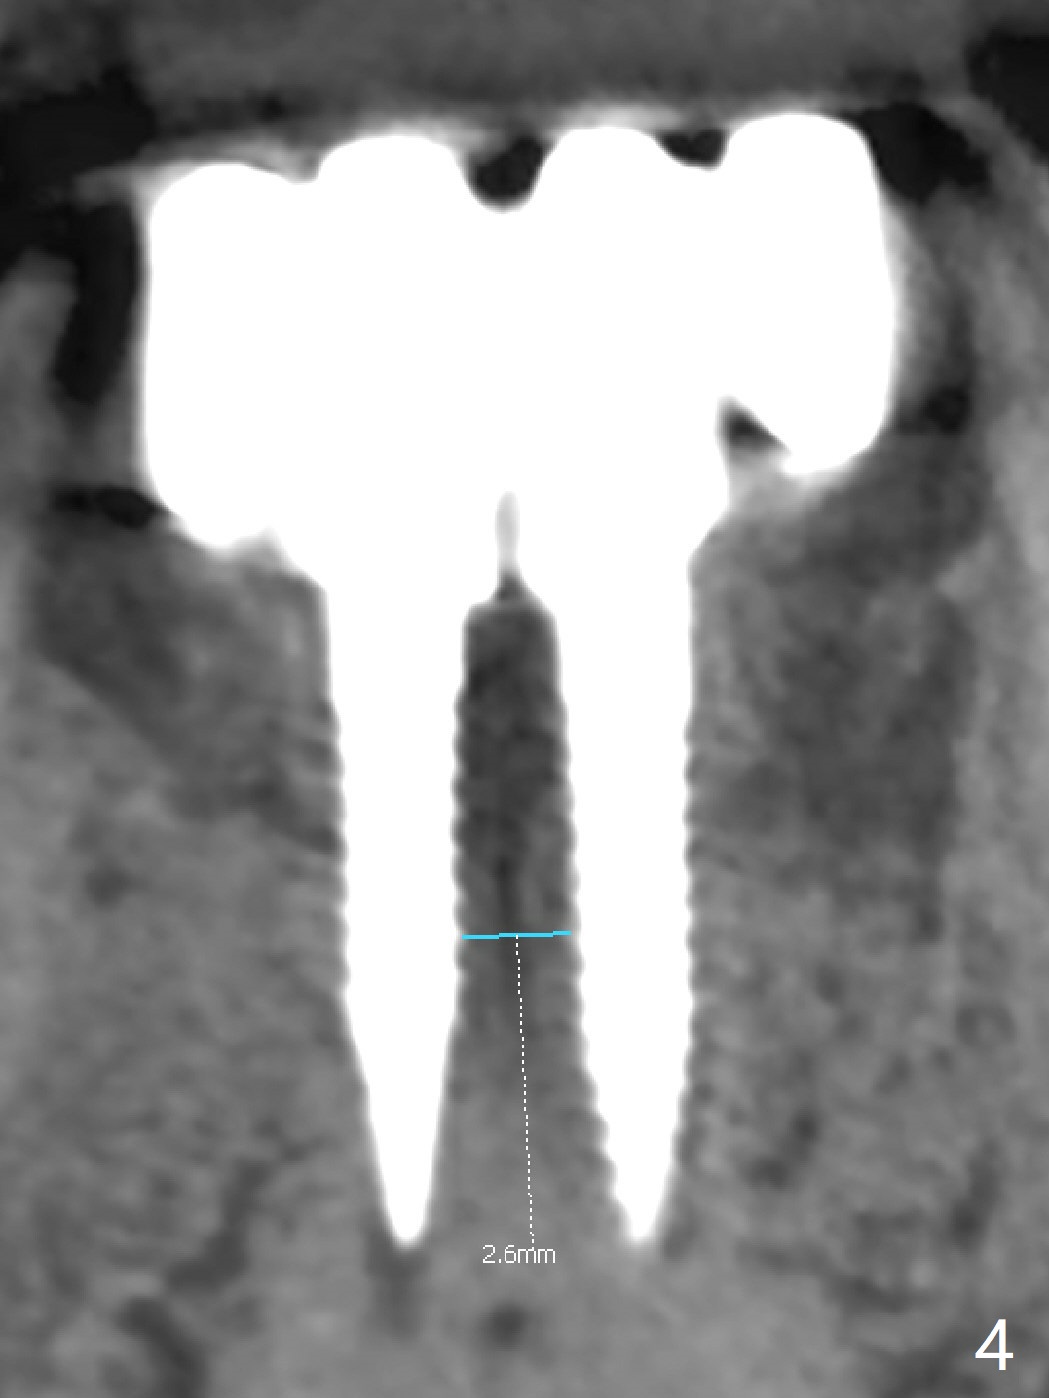

The fenetration found buccal to #25 two months post cementation persists, although asymptomatic, 4 months post cementation. Blood is drawn for PRF. In fact the implants at #24 and 25 are exposed buccal; there is limited amount of the buccal bone (Fig.1 *). After granulation tissue removal, Titanium brush is used to clean the implant threads. Allograft and Osteogen are mixed with PRF liquid to form gel, which is placed over the exposed implant threads. The bone graft is covered with a piece of PRF membrane and a piece of collagen membrane (Fig.2 C). Immediately postop PA (Fig.3) and CBCT (Fig.4) show that the implants have sufficient clearance between them. The implant thread exposure is most likely due to failure to place the implants deep enough and the implants are slightly large relative to the ridge (Fig.5-8). If the bone graft does not heal, new type of 1-piece implants (Fig.9,10 (green) smaller in diameter, 2 or 2.5 mm ) with longer abutment (pink) will be placed subcrestal buccal with guide.